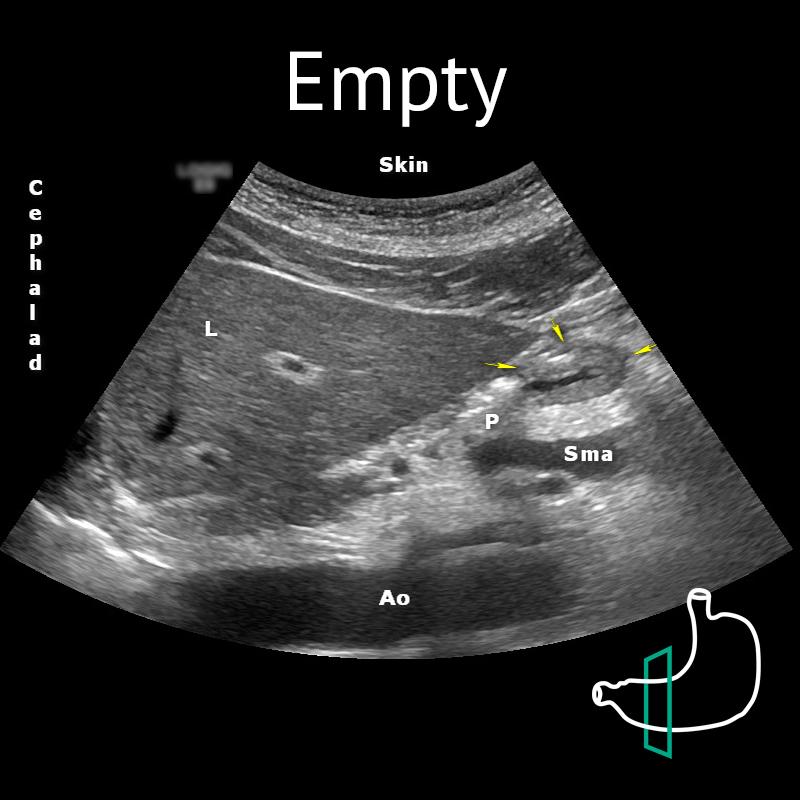

Ao: aorta; L: liver; P: pancreas; Sma: superior mesenteric artery; Yellow arrows: antrum